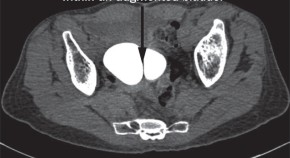

• Lower urinary tract obstruction is a morbid congenital anomaly that can be treated prenatally. Kilby & Morris discuss the importance of accurate diagnosis and case selection to optimize outcomes ofin utero intervention, before reviewing the evidence and outcome data for in uterovesicostomy, vesicoamniotic shunting and fetal cystoscopy.